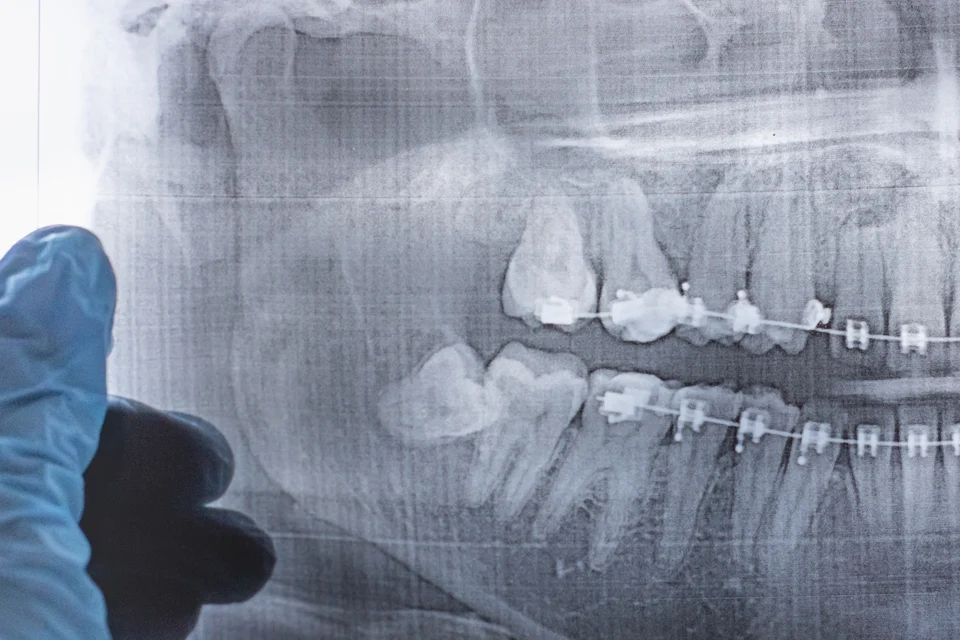

矯正牙齒的主要目的是將牙齒排列整齊,並改善咬合問題,然而牙齒矯正並非一次性的過程,在矯正結束後,牙齒仍然需要維持器的幫助來維持正確的位置,這是因為牙齒在矯正過程中已經受到移動,而周圍的骨骼和牙齦組織需要一段時間來適應新的位置,如果不佩戴維持器,牙齒就可能會回到矯正前的原來位置,導致失去矯正成果。

那麼維持器要戴多久呢?一般來說,拆掉矯正器的前12個月需24小時配戴維持器,1年後則只要在睡覺的時候再戴即可,但實際仍要以牙齒矯正狀況、年齡、醫師回診評估而定。